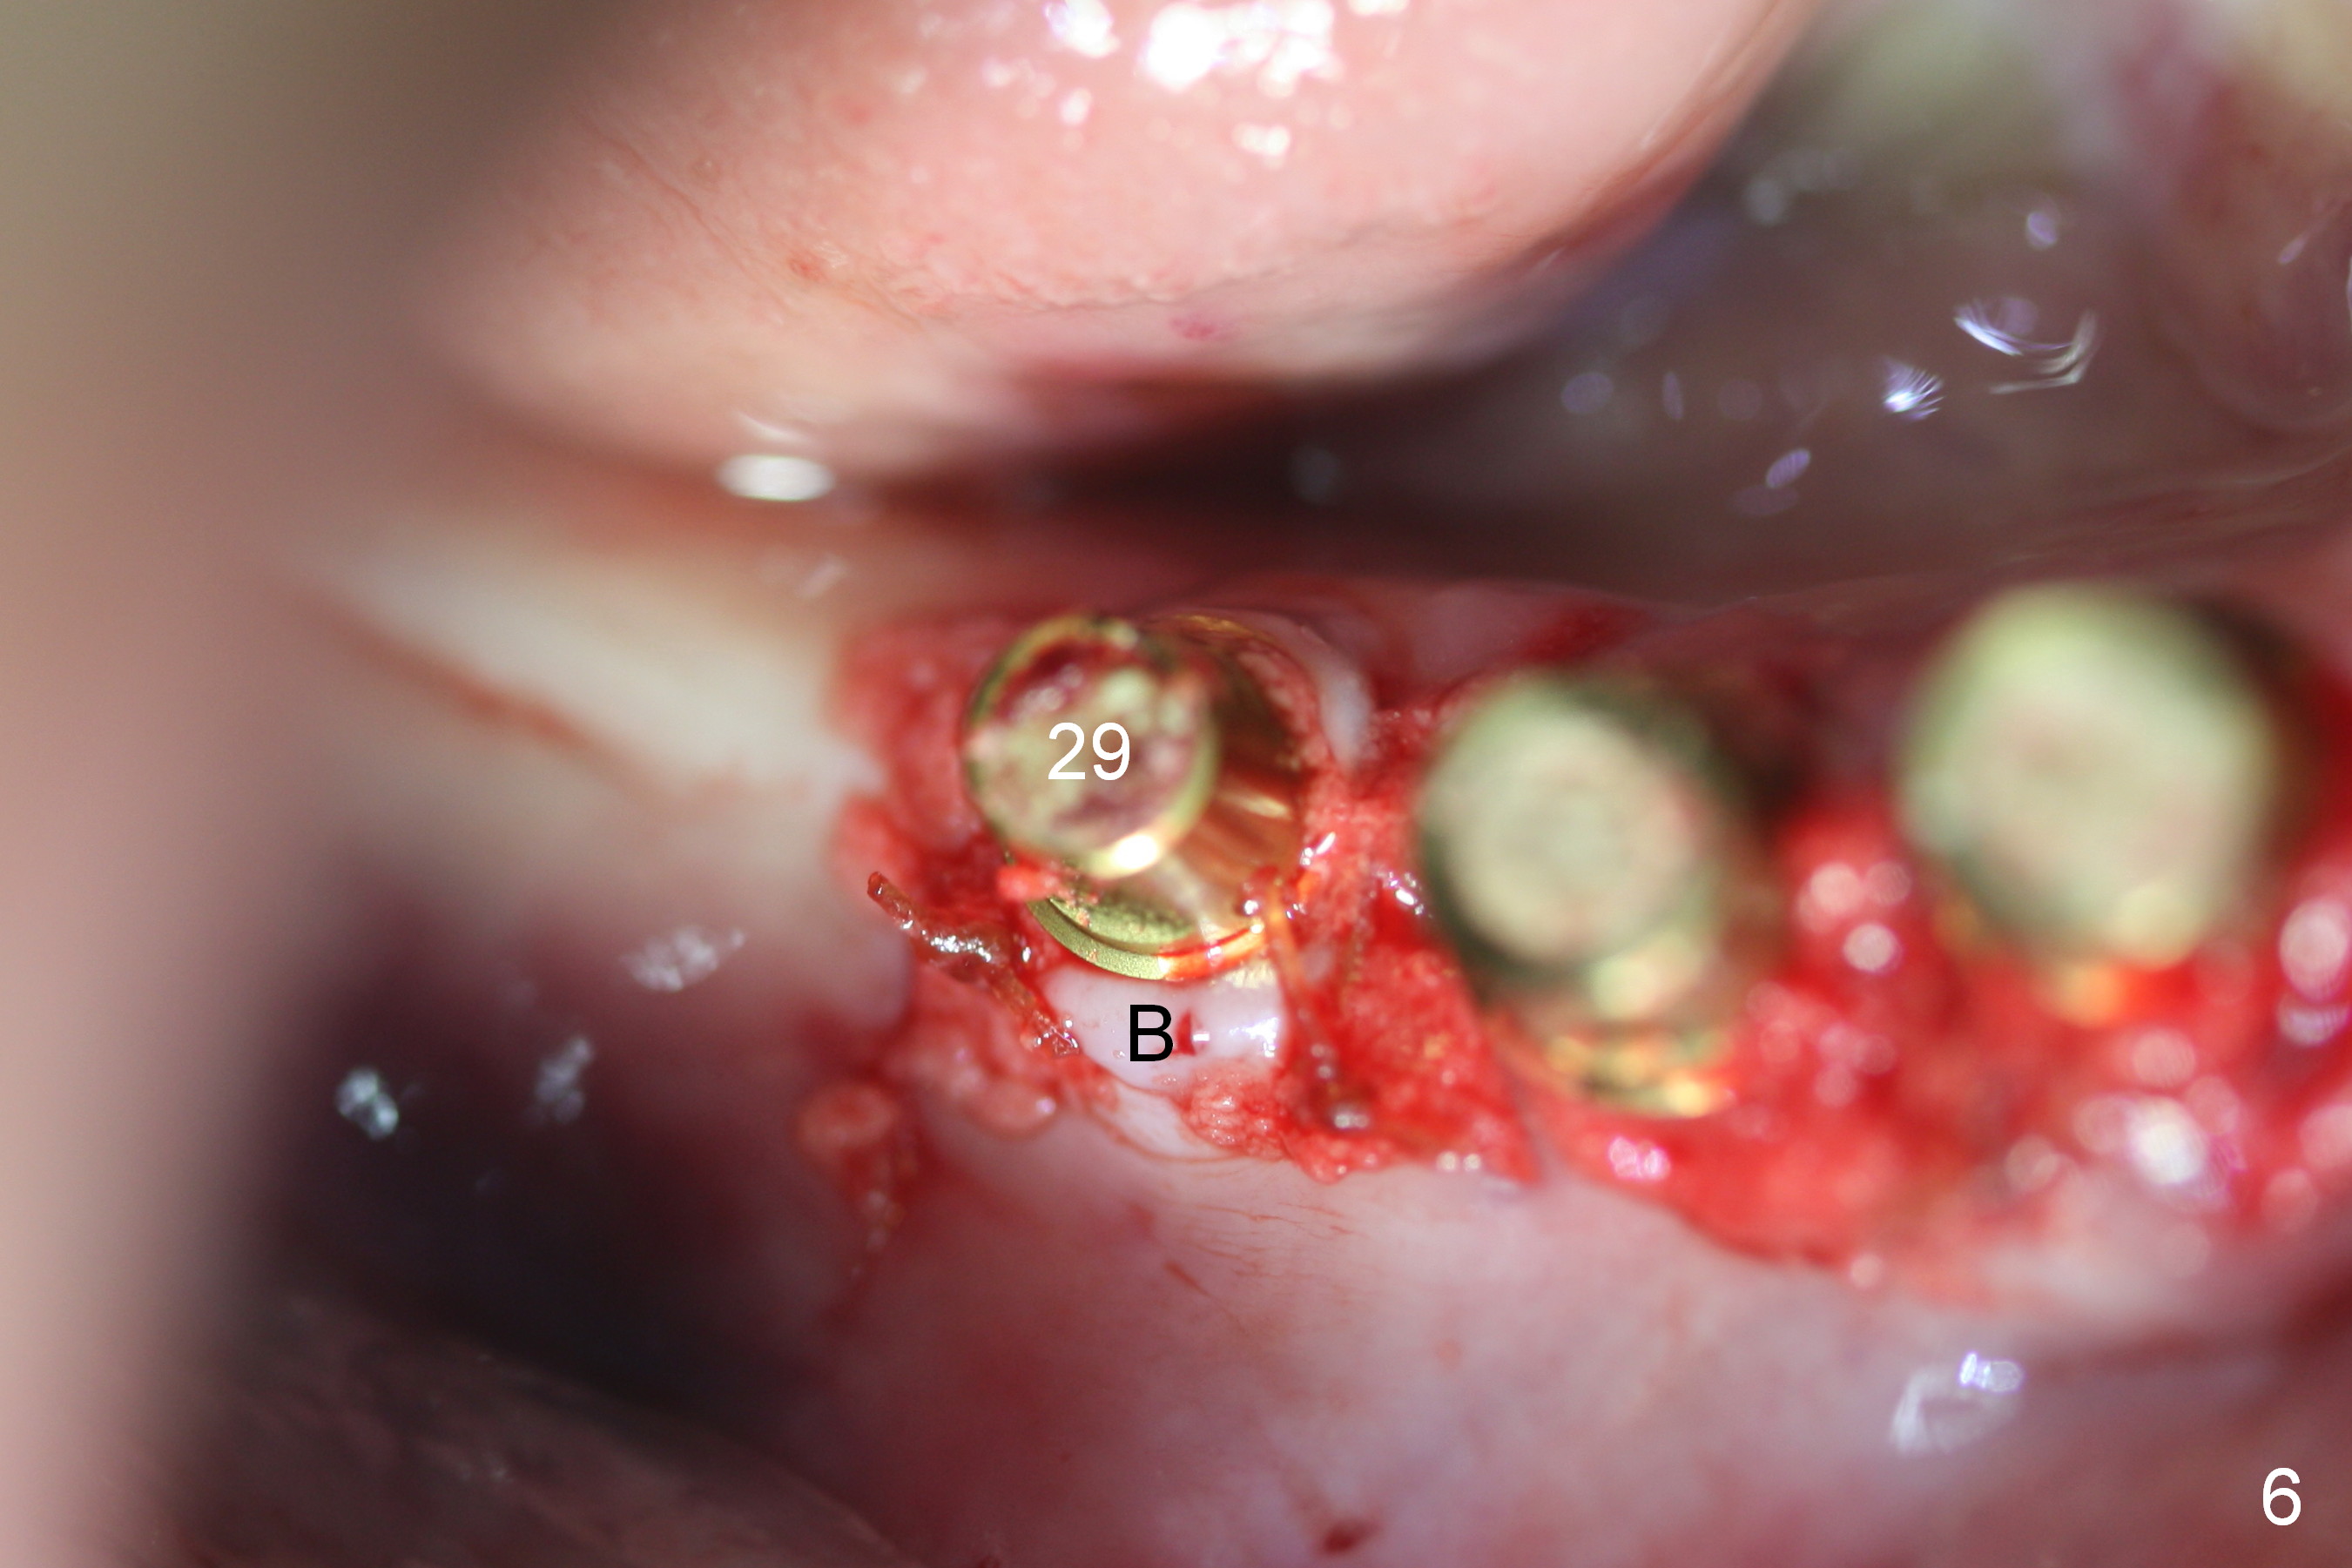

A 86-year-old man returns to office for the lower right quadrant reconstruction with implants. In addition to the immediate ones at the sites of #27 and 28 (Fig.1), how many and where else? The patient reveals that he does not plan to get an implant at the site of #3 (Fig.2). Therefore there is no need for an implant at #30. Preop CT shows that bone width is compromised at #26. So the 3rd site will be #29 (Fig.3,4). All of the 3 implants (4.5x14 mm, 4.5x12, and 4.1x12 mm) achieve primary stability (»55 Ncm). An immediate provisional could be provided, but it seems difficult to close the buccal (Fig.5 B) gaps of #27 and 28 after bone graft with the provisional. In contrast, the gingiva adapts to the implant at #29 well (Fig.6 B). Perio dressing is applied to the abutments (Fig. 7: #27-29), the edentulous space at #26 and the neighboring teeth (#23,24). It would be ideal to apply a non-resorbable membrane to the buccal opening at #27,28 (Fig.8 white line) prior to perio dressing placement. In case of dislodgement of the latter, the membrane is able to keep bone graft in place.